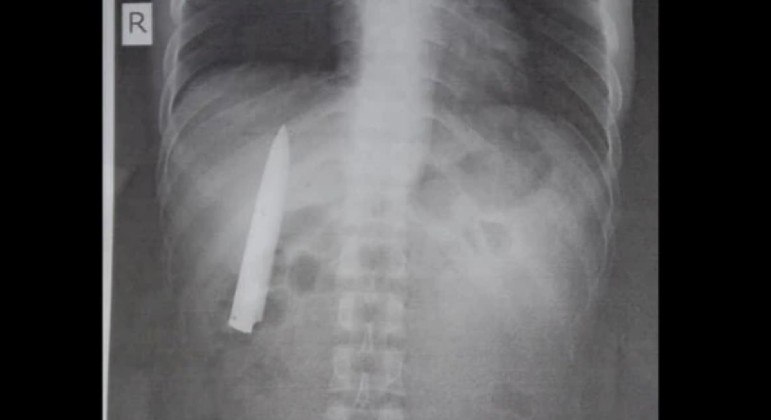

Jovem descobre lâmina cravada no peito 14 meses após levar facada

Jovem de 25 anos passou 14 meses com lâmina de faca enterrada no peito

Um jovem filipino descobriu recentemente estar há 14 meses com a lâmina de uma fa​ca enterrada no peito (acima). O objeto só veio à tona após Kent Ryan Tomao, 25, ter sido submetido a um exame clínico ocupacional, exigido para o emprego que ele conseguiu em uma mina da província de Agusan del Sur.